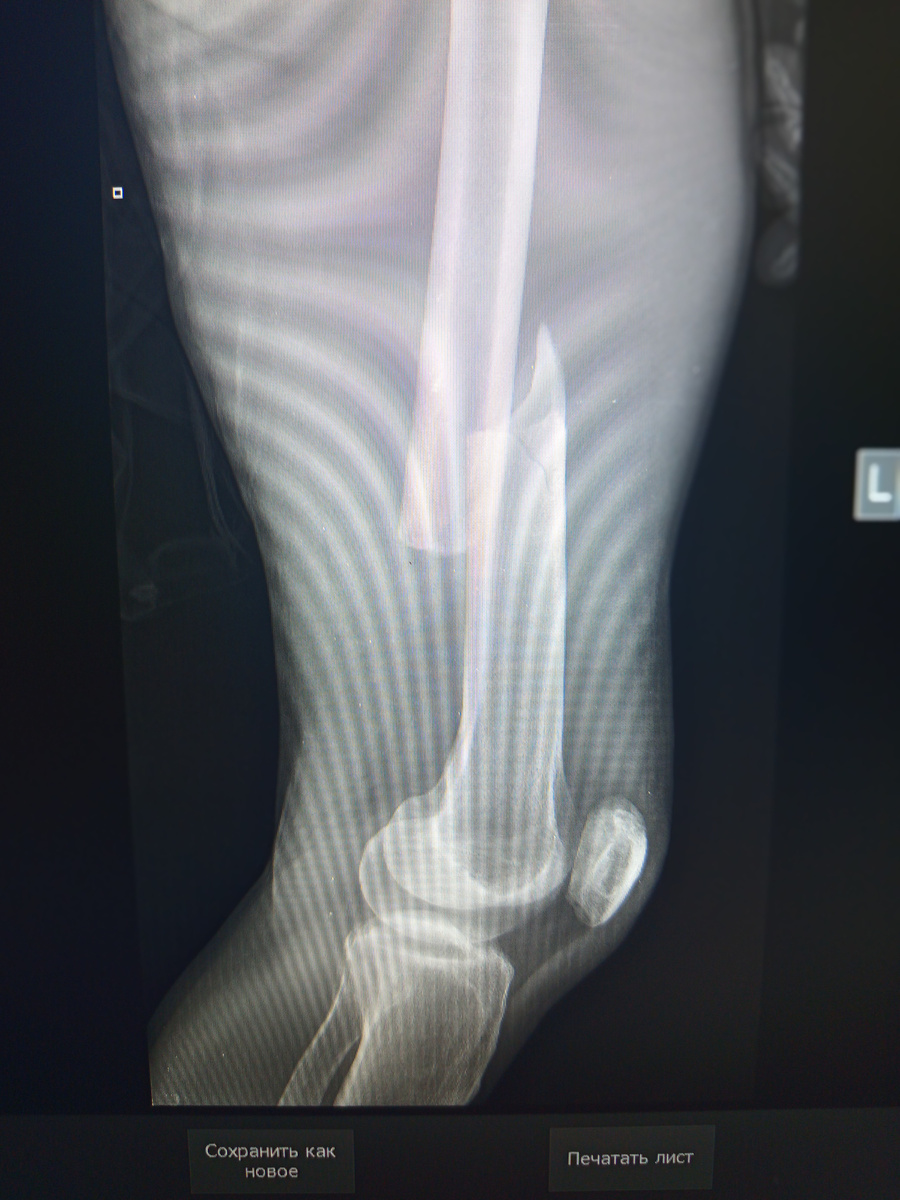

И , что видно при снимке? Перелом локтевого сустава с продолжением в локтевой кости.

-6

Если бы врачи проводили осмотр , как положено, то можно избежать ненужных снимков.